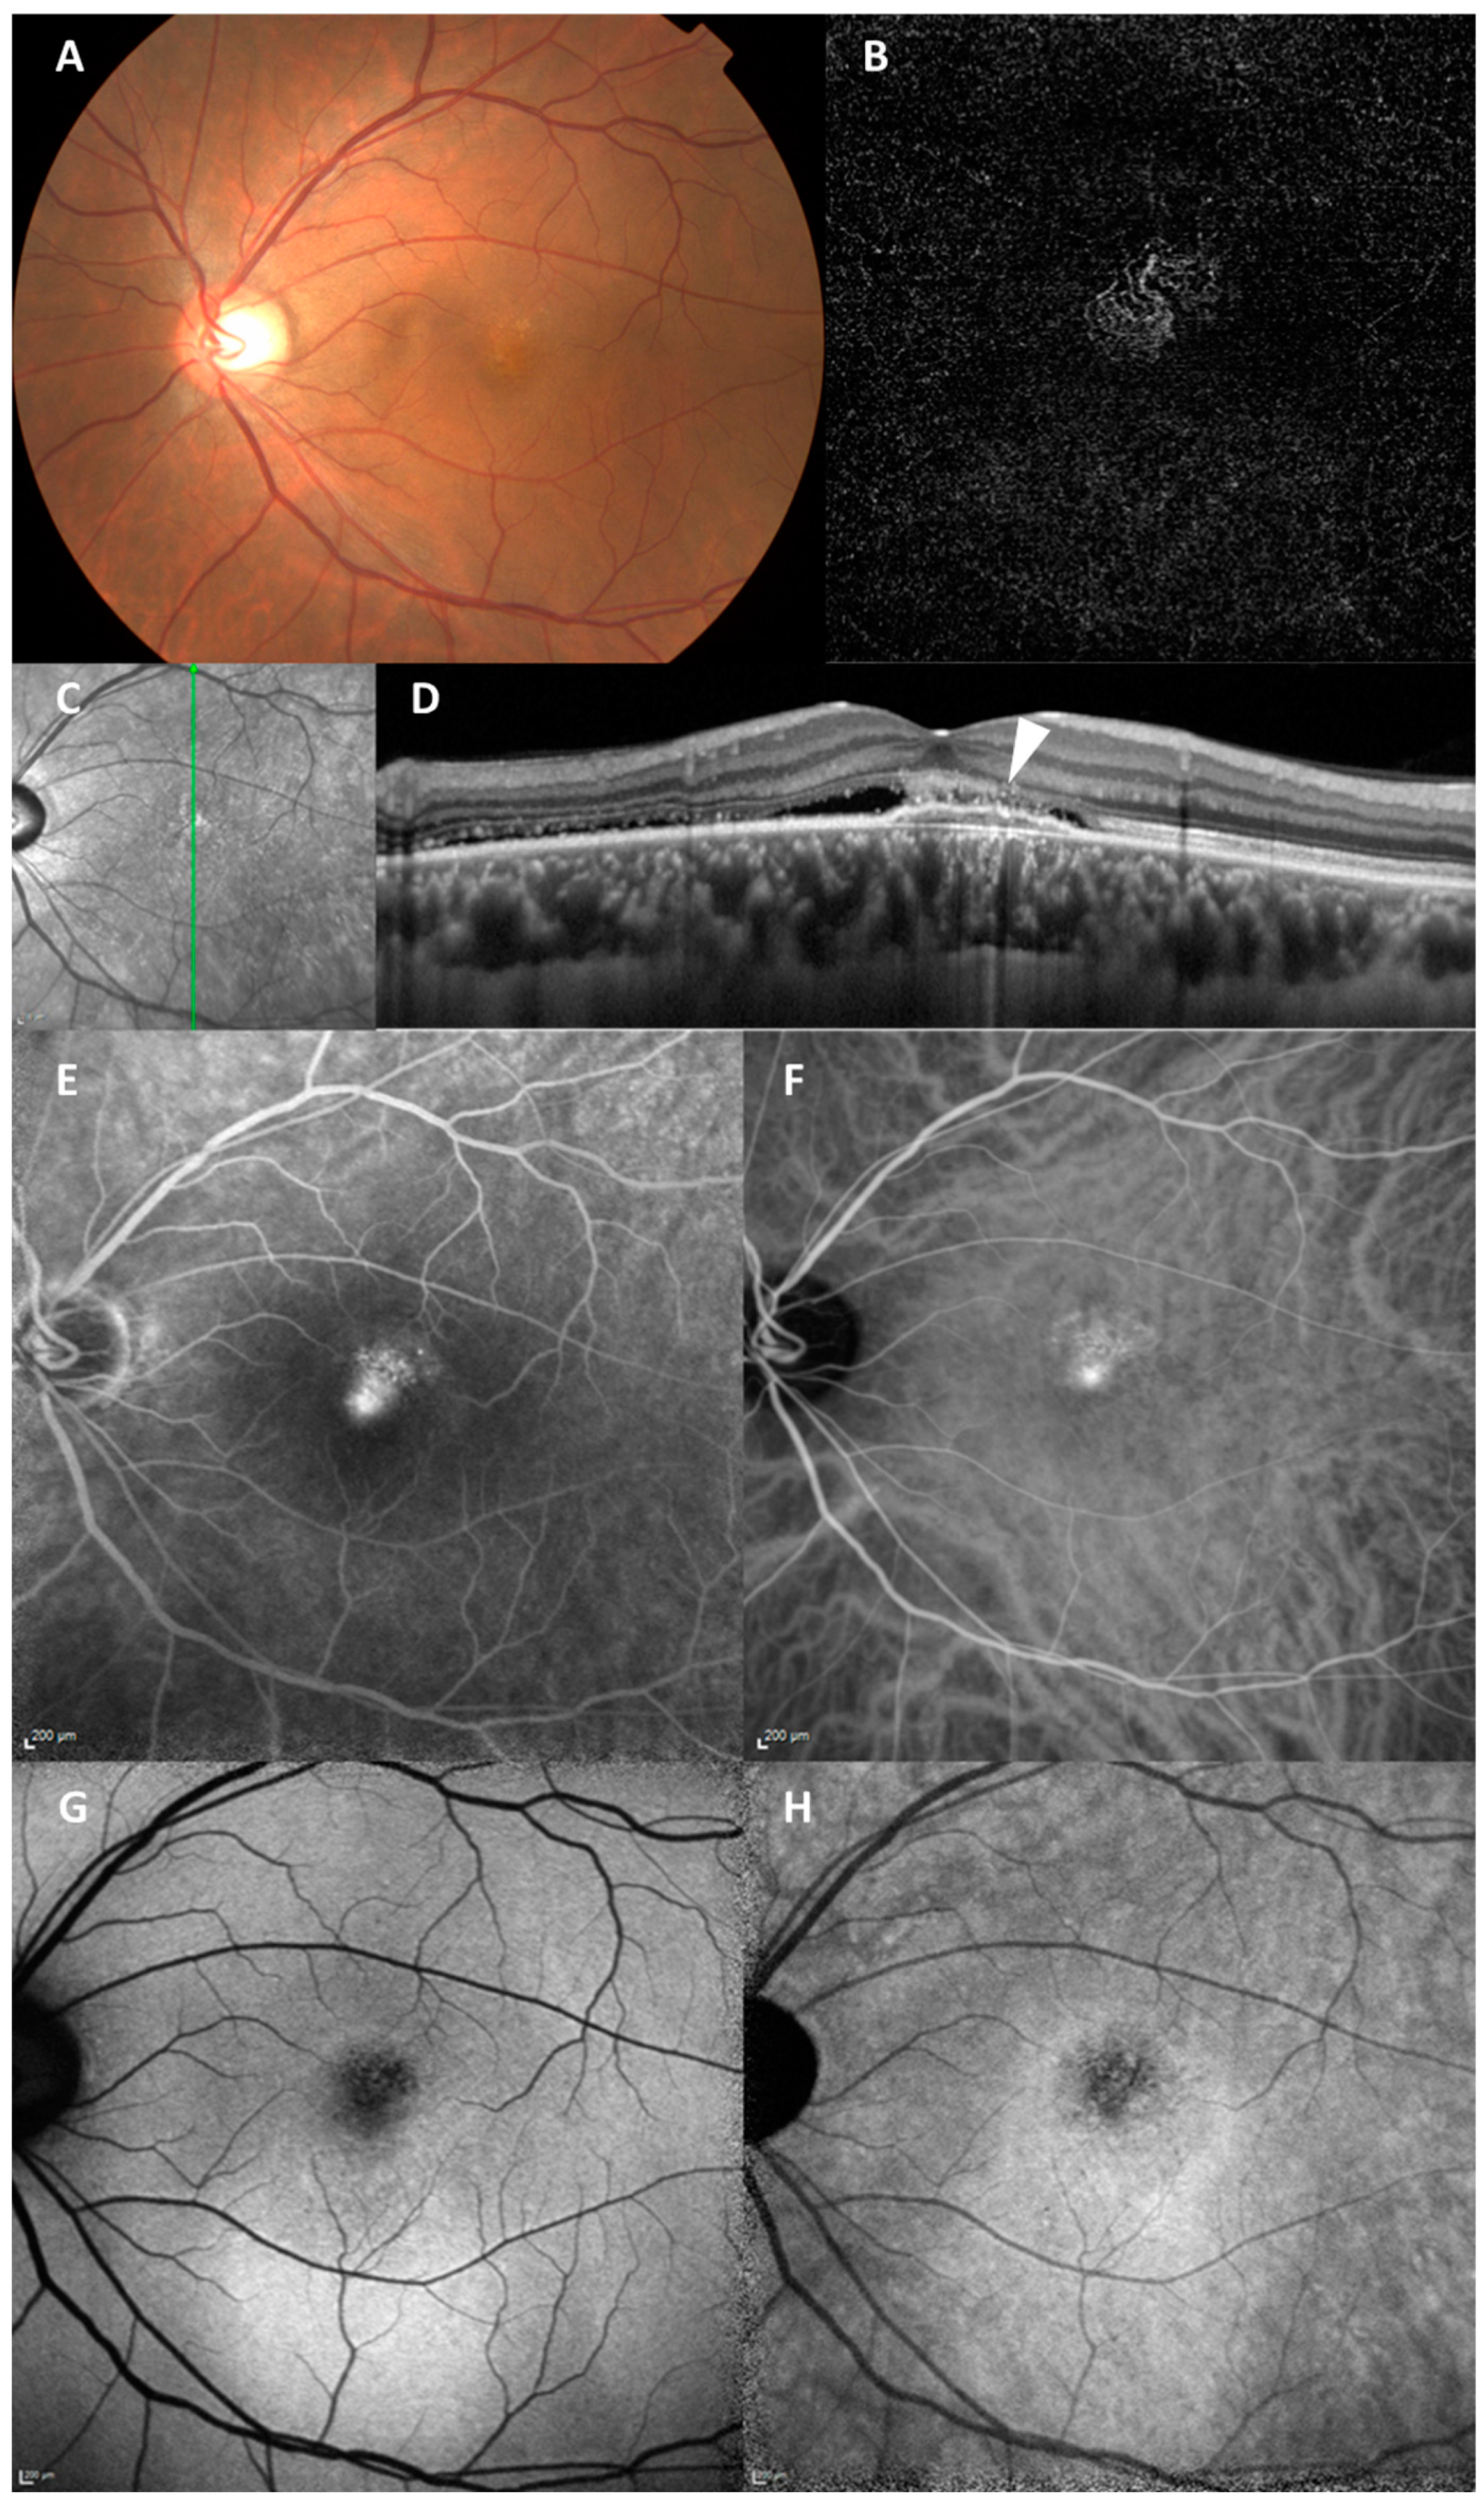

Figure 4.

A representative case of PNV with multimodal imaging. A 47-year-old Asian male with treatment-naïve PNV. (A) Color fundus photograph showing reduced fundus tessellation with no drusen. (B) OCTA showing MNV. (C) Near-infrared fundus image with the vertical green line through the fovea corresponding to the B-scan on the right. (D) EDI-OCT showing SRD and RPE elevation consistent with type-1 MNV (arrowhead). (E) FA showing hyperfluorescence indicating leakage from MNV. (F) ICGA showing hyperfluorescence indicating MNV. (G) SWAF showing hyper AF pattern and hypo AF in the area with MNV. (H) IRAF showing the hyper AF pattern and hypo AF in the area with MNV.